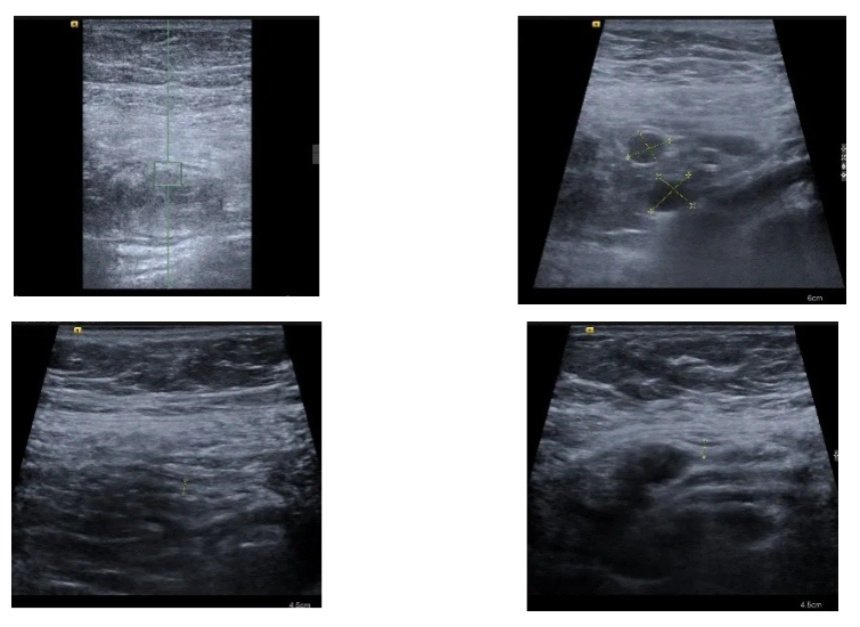

于是第一时间收入病房,完善了一系列检查,考虑小肠炎症,予禁食、抗感染、营养支持后症状逐步好转,在治疗过程中,考虑到随访过程中若反复进行CT检查存在一定顾虑,于是在入院时和症状好转后分别进行了肠道超声检查,来帮助医生们评估肠道炎症的情况。

入院时患者的肠道超声报告提示:

•小肠5区肠壁增厚,Limberg I,肠系膜周围见多发肿大淋巴结;

•小肠6区肠壁增厚,Limberg I,盆腔内、小肠周围见少量积液;

•升结肠、横结肠、降结肠、乙状结肠未见明显异常。

在进行治疗、患者症状基本消失后复查了肠道超声,上述节段的小肠炎症基本在超声下都消失了,再加上患者症状也基本消失,医生们在治疗上进行了调整,逐步开放了饮食,同时进行了其他一系列的检查明确了诊断,患者也平稳出院了,近期随访下来患者没有出现症状反复,生活状态良好。

在这位患者的整个诊治过程中,肠道超声发挥了举足轻重的作用,避免了重复的CT检查,帮助医生们进行临床诊断、评估患者的病情,及时调整治疗策略,使得医生们更加游刃有余。